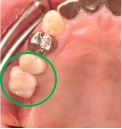

Before

※赤丸は、歯根が破折していたため抜歯しました

※黄色丸は、2006年10月に埋入したインプラント

After

※緑丸は、今回埋入したインプラント